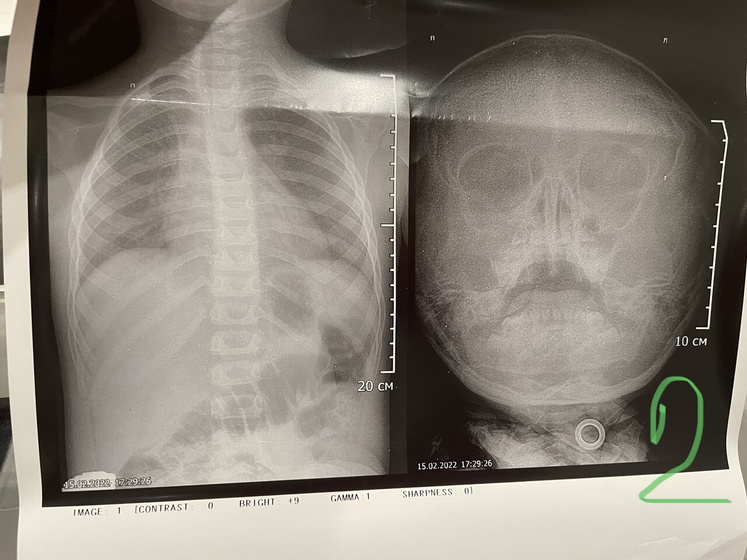

Двусторонний риносинусит у обоих, у младшего + бронхит. У меня двусторонний полисинусит (D<S), ринит. А началось всё с меня 2,5 недели назад, писала тут что с 6 утра 38,3, днём до 39. КТ, анализы кровь моча биохимия в норме относительно, узи почек в норме — из-за чего темп непонятно. Через два дня в воскресенье закладывает нос, напрочь. И вот пошла третья неделя моего заложенного носа, местами дышу как рыбка ртом хватая воздух. У старшего нос забился как и у меня где-то с неделю. У младшего непонятно, но тоже немного сопли, начал покашливать. По итогу, вчера съездили на рентген в детскую поликлинику, я тоже напросилась (ибо к Лору времени, желания и сил у меня нет идти). Итог на фото и в тексте.